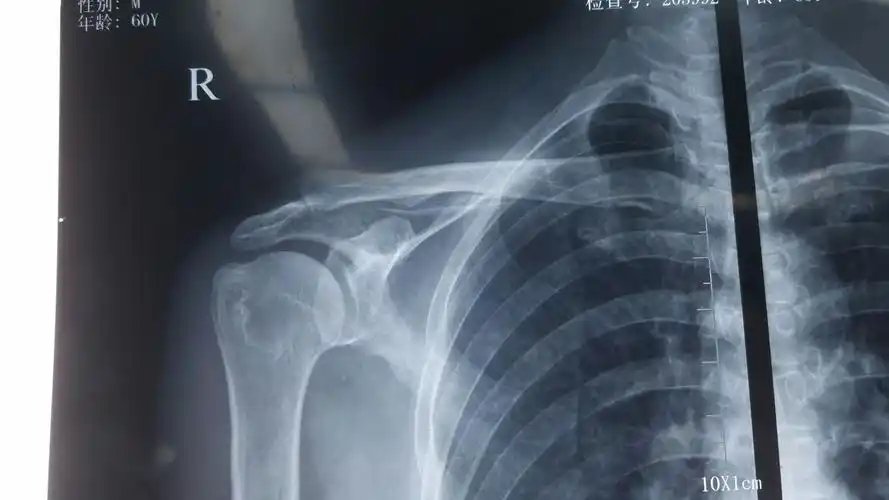

肩关节镜下肩峰成行,肩袖修补术